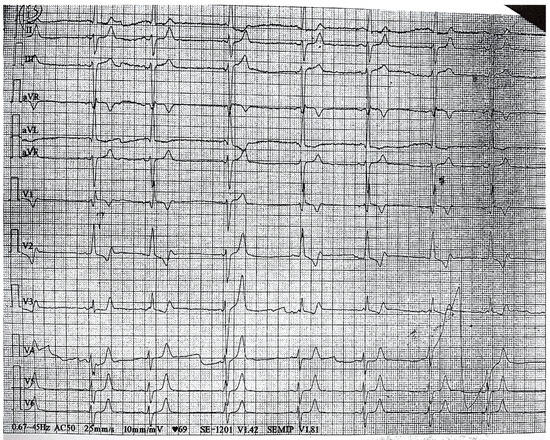

2. Case Presentation